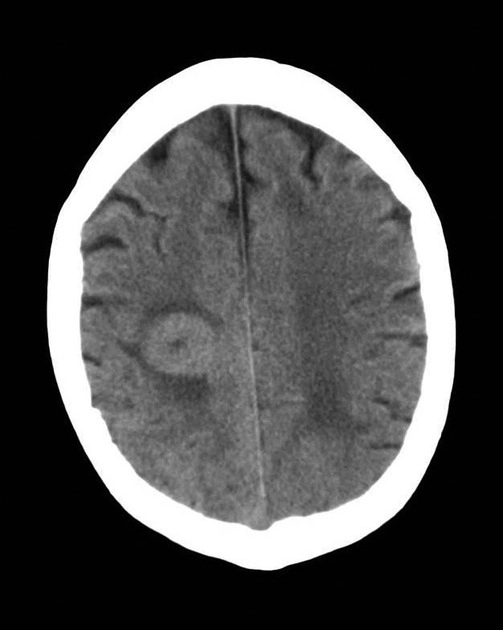

Di căn nhu mô não (Parenchymal metastases)

• Di căn nhu mô não (Parenchymal metastases)